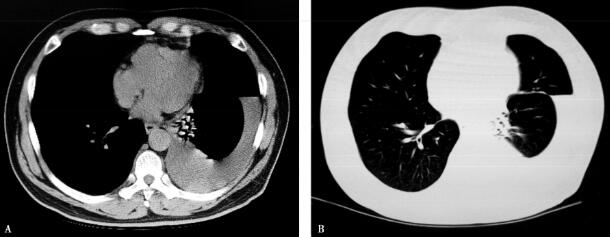

1.胸部CT(2011年12月19日引流900ml胸腔积液后):左侧胸腔积液伴左肺下叶膨胀不全,左侧叶间积液,纵隔及左肺门增大淋巴结,心包少量积液(图1A纵隔窗、B肺窗)。

图1